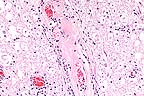

Suppurative adrenalitis in a foal with Actinobacillus equuli septicemia. (HE, 400X, 70K).

1. Liver: Multifocally, distributed in the hepatic parenchyma, there is a moderate number of variably sized microabscesses. 2. Kidneys: The cortical tissue contains numerous glomeruli undergoing necrosis caused by a severe multifocal suppurative infiltrate. Numerous glomeruli are completely obscured by suppurative infiltrates characterized by degenerate neutrophils and necrotic debris. 3. Adrenal gland: The adrenal cortex is diffusely, severely hemorrhagic and contains a moderate number of small foci of necrosuppurative inflammation.

AFIP Diagnosis: Adrenal gland, cortex: Necrosis and hemorrhage, diffuse, with multifocal suppurative adrenal adenitis and capsular fibrin thrombi, Standardbred, equine.

Conference Note: Actinobacillus equuli is a gram-negative, facultative anaerobic bacillus. It is found worldwide and is a normal inhabitant of the equine intestine. Actinobacillus equuli primarily affects immunosuppressed foals or those with failure of passive transfer. In the foal, A. equuli causes fibrinopurulent arthritis, omphalophlebitis, suppurative nephritis, pneumonia, and abscesses in many other organs. This organism is also an important cause of fetal death and abortion in horses.

The hemorrhage and thrombosis in this case were most likely caused by endotoxins. The effects of endotoxins on endothelial cells and the resultant damage and initiation of the coagulation cascade is discussed in detail in Case 1 of this conference.